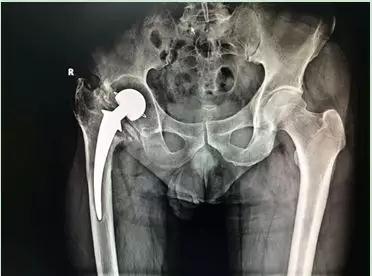

術(shù)前X線:髖關(guān)節(jié)假體已松動,假體周圍大量骨溶解

疼痛性假體松動是翻修手術(shù)最常見的適應(yīng)證,典型表現(xiàn)是起步時疼痛,髖臼假體的松動通常引起腹股溝區(qū)的疼痛,而股骨假體的松動則導(dǎo)致大腿或膝部疼痛。該患者27年前因髖關(guān)節(jié)結(jié)核行髖關(guān)節(jié)置換術(shù),近年來出現(xiàn)患肢短縮及行走疼痛,在我院診斷為“全髖關(guān)節(jié)置換術(shù)后假體松動”。

但是“松動”并不意味著假體容易取出,大多數(shù)情況下需要用各種方法用力將假體取出。同時清除初次手術(shù)中的骨水泥是髖關(guān)節(jié)翻修手術(shù)中最為費(fèi)時和危險的。而由于磨損松動或者感染引起骨缺損是髖關(guān)節(jié)翻修中的最主要問題。該患者術(shù)前X線及CT檢查顯示存在大量的骨缺損,我科率先使用鈦合金骨小梁填充塊重建髖臼,完美的解決了髖臼的骨缺損問題。